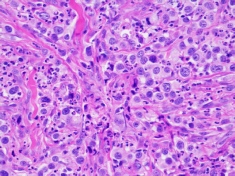

Biopsy (histopathology) from a dog’s mast cell tumour (high grade).  Features like the rate of cancer cell division, and invasiveness of normal tissue allow the pathologist to ‘grade’ the tumour and predict its behaviour. The ‘completeness of excision’-whether the vet got it all, can also be evaluated.